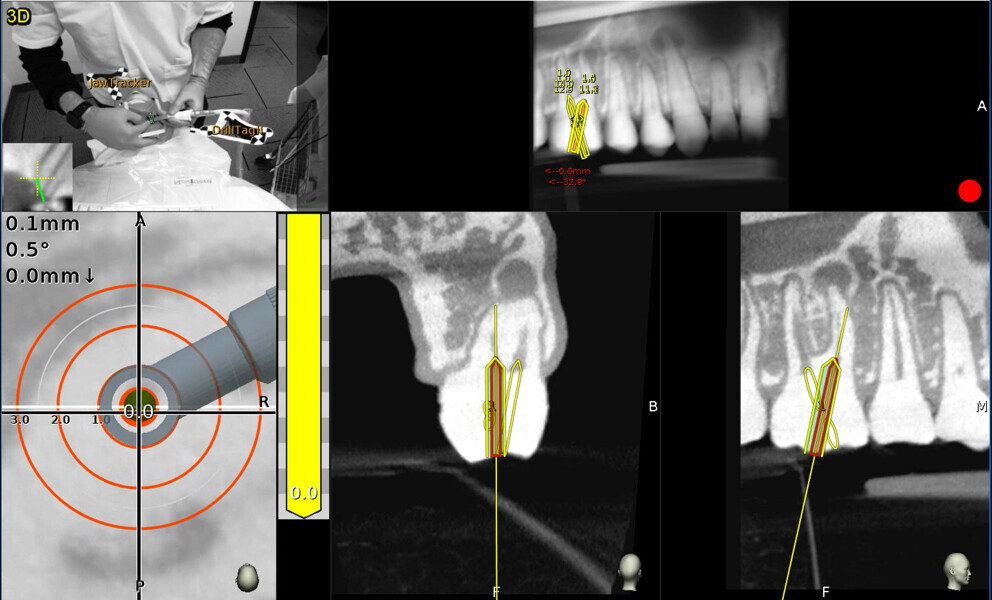

Fig. 3: The screen is divided into (1) panoramic view, (2) 3D reconstruction, (3) axial view, and (4) buccolingual and (5) mesiodistal section views.

Fig. 9a: Calcified central incisor: (1) the drill is green; (2) the central axis of the glide path or osteotomy; (3) the depth indicator; (4) the angle between the drill and central axis of the planned osteotomy. When the drill and the central axis overlap, the depth indicator turns yellow. (Courtesy of Dr Bobby Nadeau)

Fig. 9b: Maxillary molar: the planned canal location is on target (yellow: 0 mm). (Courtesy of Dr Bobby Nadeau)